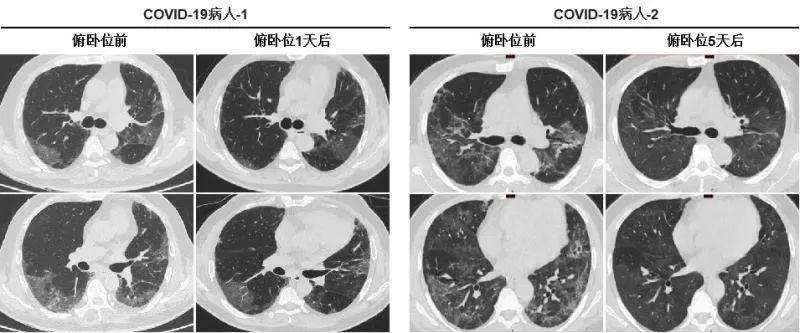

随着COVID-19的全球流行,截至2020年8月6日,共有19,093,957人感染,死亡713,408人,死亡率为3.7%。许多COVID-19患者因严重缺氧而死亡,找到一种简单有效的COVID-19患者治疗方法显得尤为重要。从2020年2月1日至2020年4月30日,共有60名COVID-19严重缺氧患者入组。23例患者采取早期俯卧位,37例患者未采取。在俯卧位组,30分钟后脉搏血氧饱和度(SpO2)从91.09±1.54%增加到95.48±1.73%(P <0.01)。呼吸频率(RR)从28.22±3.06次/分钟降至24.87±1.84次/分钟(P <0.01)。ROX指数从3.35±0.46增加到3.96±0.45(P <0.01)。然而,非俯卧位组的SpO2、RR和ROX指数没有显著差异。此外,早期俯卧位也可明显改善一些患者的CT成像表现。随访90天后,俯卧位组有10例(43.5%)COVID-19患者死亡,而非俯卧位组有28例(75.7%)COVID-19患者死亡。对于早期俯卧位改善缺氧的潜在机制,推测可能是由于血流重新分布引起的,水肿液在重力作用下重新分布到腹侧,萎缩性肺泡在俯卧位时重新开放,导致V/Q改进。总之,这项工作将有助于临床医生利用俯卧位治疗严重缺氧的COVID-19患者,降低严重缺氧的COVID-19患者的死亡率,对于COVID-19患者的治疗有一定的指导意义。